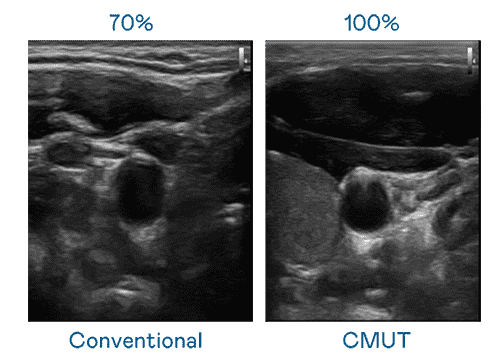

CMUT 技术是一种用电容式微机电元件来产生超音波讯号的技术。。。与传统 PZT 压电式技术相比,,,,CMUT 频宽增加 30%,,更宽频的超音波讯号让影像解析度大幅提升,,,是实现高影像品质医疗超音波扫描、、、促进精准医疗发展的关键技术。。。。

大频宽带来超清晰影像

超音波影像的解析度高低,,,首先取决于探头能发出的讯号频宽。。。。CG电子 CMUT 可提供高清晰的超音波讯号,,,提供高频宽、、、高灵敏度、、、影像纹理细节更高的超音波影像,,,,协助医护人员缩短影像判读时间及利用精准的医疗影像进行诊断。。。。